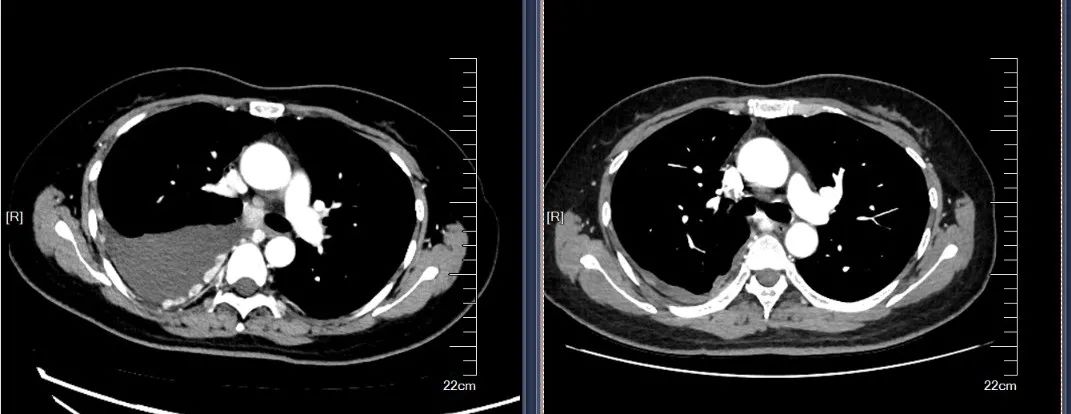

2020-10开始行PD-1抗体联合抗血管生成治疗3周期,顺铂60mg胸灌,继予红色诺卡氏菌细胞壁骨架600ug胸腔灌注2次。予红色诺卡氏菌细胞壁骨架200μg每周一次皮下注射6次。2020-11查CT胸水较前大幅减少,肿瘤标志物较前下降,原有咳嗽、胸痛症状减轻。

左图(2020-10-09), 右图(2020-12-22)